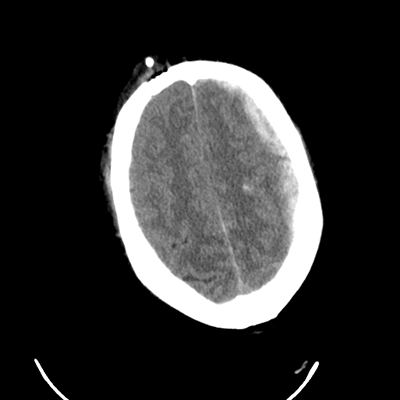

In the ED, initial vitals are notable for BP 110/76, HR 114, SpO2 92%, T 37C. Non-contrast head CT (shown here) as well as CTA head/neck are obtained. You are then consulted. You ask them to hold his propofol and fentanyl so that you can properly examine him once you arrive.

What do you make of his head CT?

The main abnormality seems to be a thin left-sided convexity SDH (thickness about 3mm at the narrowest point, about 6mm at the thickest point closer to the vertex) with some pneumocephalus. There's very slight midline shift (about 2.5mm). You also made sure to look at the bone window, especially since those bubbles of air caught your eye. There's a comminuted calvarial fracture frontotemporally there too. While not shown here, his vessel imaging was fortunately normal.